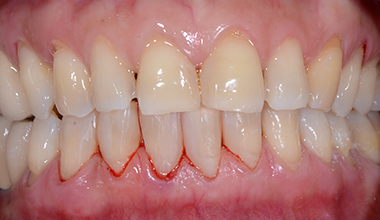

치료 전 -

치료 후

다이아스테마 - 앞니 벌어짐